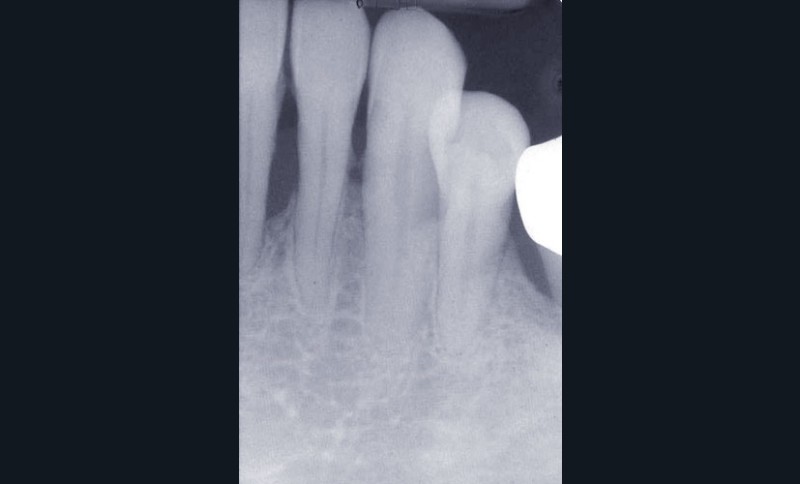

Une patiente âgée de 45 ans consulte à la fin des années 1990 avec une contention en échelle au maxillaire afin de soulager les mobilités des dents antérieures.

Les examens cliniques et radiographiques montrent une parodontite chronique généralisée (fig. 1a à m).